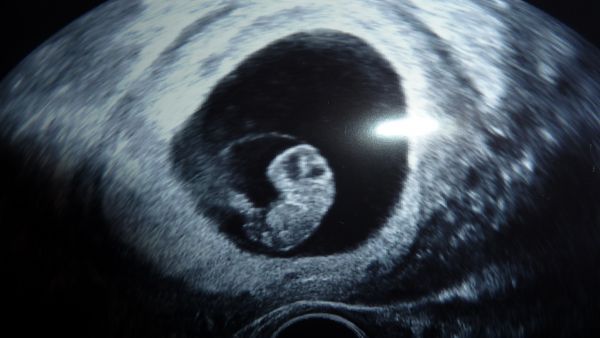

Dnes opět návštěva pohotovosti a to, že jsem se tam teda načekala, měli tam nějaký zmatek, tak protekce neprotekce. Zkejsla jsem tam 3 hodiny :-(, Ale to je vedlejší. Návštěva byla opět kvůli krvácení :-( Miminko je ale v pořádku i mi mávalo ručičkou, tak se Dr. smála. dle ms 8+3, dle utz 8+5, mimi má18,7mm. Důvod krvácení teď byl krásně vidět. mám nad vntiří brankou hematom 17x12mm. Takže nadále vše jak mám a myslet pozitivně. Snad vymizí a nestáhne mimíska. Přikládám foto, které jsem fotila foťákem, tak nevím jak to bude lépe vidět.